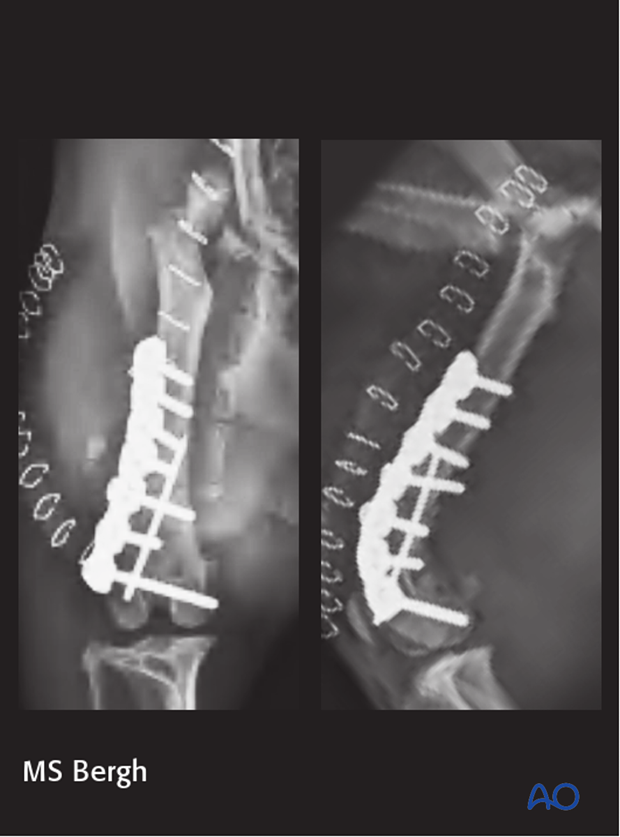

10-year-old MC Jack Russell Terrier of 6 kg.

Stepped on by owner 1 week before presentation.

The fracture was repaired using a 2.0 mm distal femoral plate in bridging fashion.

7-week postoperative radiographs.

The patient reported fully healed at the 12-week postoperative radiographic control.